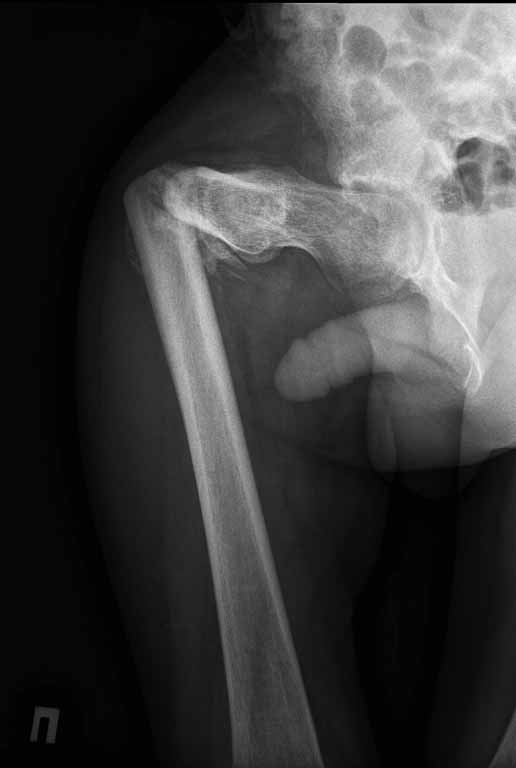

Пациенту 22 года. Травма в июле 2010г, лечился в районной больнице. К нам попал в апреле 2011г.Тяжелая сочетанная травма (29.07.2010): тупая травма живота с повреждением внутренних органов. Закрытая травма грудной клетки с переломом ребер. Пневмоторакс справа. Тяжёлая позвоночно-спинномозговая травма. Закрытый осложнённый переломо-вывих С5 позвонка. Верхний парапарез, нижняя параплегия, нарушение функции тазовых органов по типу недержания. Цекостома. Пролежень левой ягодичной области. Неправильно консолидированные переломы верхних третей обеих бедер. Застарелый вывих левого бедра.Осложнение: Поддиафрагамльный абсесс слева, забрюшинного пространства. Свищ желудка и ободочной кишки. Синегнойный сепсис. Двухстороняя пневмония. Но это уже анамнез.Пациент был неоднократно оперирован на органах брюшной полости и осложнениями с ними связанными.

В ягодичной области слева глубокий пролежень размером 2х2см, дном является вывихнутая головка бедра. Неврологически в нижних конечностях динамика положительная, появились движения в правой стопе, чувствительность в стопах.По переломам бедер: подвижности в местах переломов нет, снимки высылаю.

Мне кажется, что нудно начать с резекции головки левого бедра (как минимум - вы устраните очаг хр. инфекции) далее заниматься закрытием стом и правой стороной (судя по неврологической динамике).К левой стороне можно вернуться позже, если понадобится.